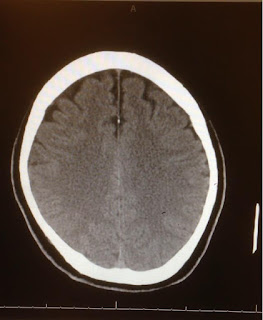

On another note, Consciousness is defined medically as wakefulness and awareness (Plum & Posner 1983). Its opposite is called Comatose. When a person is in a COMA, it means that he is not awake and aware of himself nor his environment. Thus this means the person is no longer conscious? What about a person in a vegetative state? When a person is awake but unresponsive with no awareness of himself or the environment, is the person still conscious? Other factors like motor impairment, facial paralysis, incontinence, verbalization, olfactory, vigilance and pain contribute to the presence/absence of consciousness. To complement these behavioral diagnoses, neuroimaging techniques are implemented such as PET (positron emission tomography), MRI (magnetic resonance imaging) and EEG (electroenceohalography)